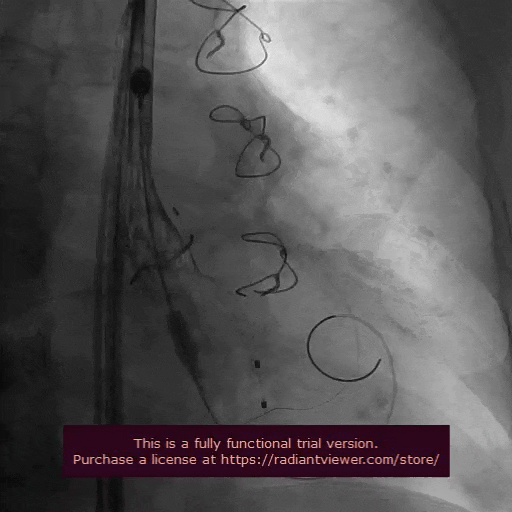

主动脉根部造影

瓣膜初始定位

瓣膜释放到2/3,造影确认位置合理

完全释放后造影评估